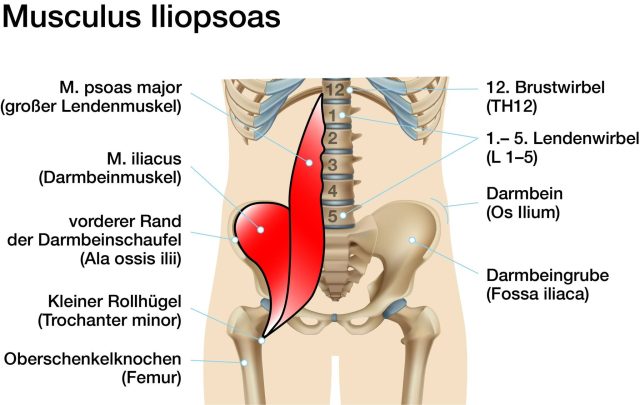

1- Liên kết MẠC CƠ (Fascia & Myofascia)

– Thận nằm sau phúc mạc, được bao quanh bởi Gerota fascia

– Mạc cơ tương liên: Fascia của Cơ thắt lưng – chậu (Psoas – Iliacus)

– Thoracolumbar fascia (mạc ngực – thắt lưng): nối Thận – Cột sống – Cơ dựng sống – Cơ chéo bụng)

2- Liên kết cơ – xương – khớp: Cơ liên quan trực tiếp:

– Cơ Psoas Major, Quadratus Lumborum, cơ dựng sống

(Hình ảnh đính kèm: )